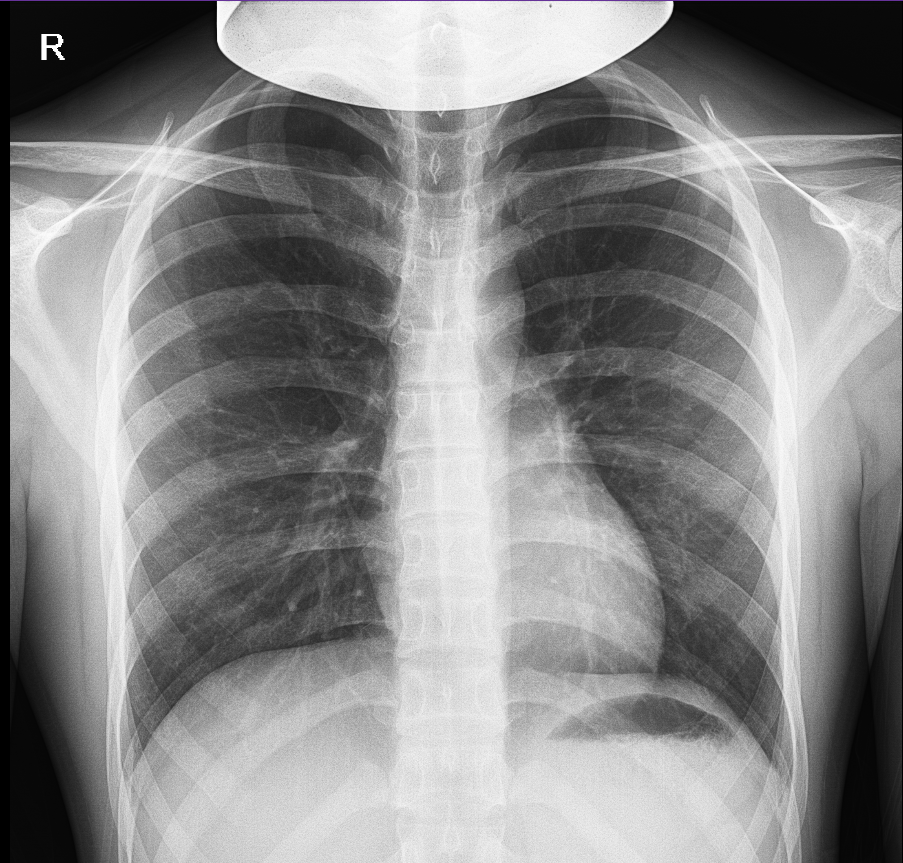

嘉利达医疗DR检查影像数据集

医疗DR检查影像数据集,包含匿名化的患者基础信息(性别、年龄区间、检查部位和检查报告)内容,可应用在影像诊断、医疗、决策支持系统、生成等方面。如:1.影像诊断:AI可以通过深度学习···

广州数据交易所